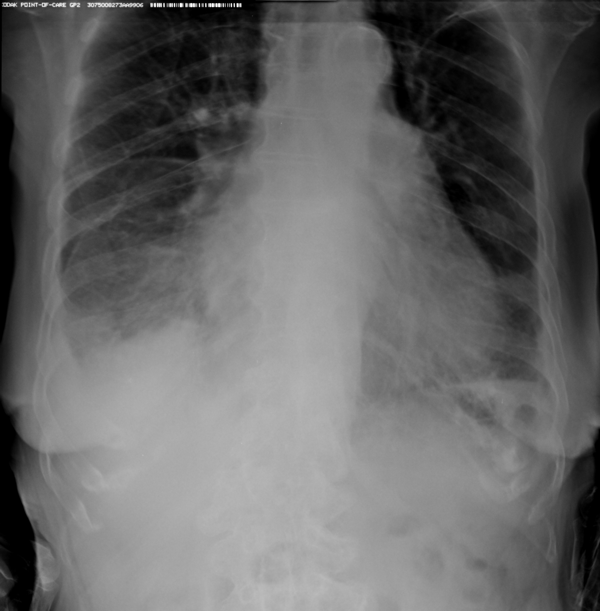

| Диагностика пневмонии и повреждений грудной клетки на дому

Рентгенография легких на сегодняшний день остаётся одним из наиболее часто назначаемых методов диагностики заболеваний лёгких. Рентгенограммы грудной клетки являются неотъемлемой частью диагностического процесса в терапии, хирургии, анестезиологии и профессиональных болезнях. Важное значение рентген легких имеет при ежегодных профилактических осмотрах населения и рентгенконтроле групп риска. Наиболее частой причиной, по которой врачи различных специальностей, в первую очередь врачи терапевты поликлиник, назначают рентген легких, является подозрение на пневмонию. Пневмония – простыми словами воспаление легких – острое воспаление легочной ткани инфекционного происхождения с преимущественным поражением альвеол и интерстициальной ткани легкого. При этом жидкость скапливается в просвете альвеол, что ведет к уменьшению дыхательной поверхности легких. Пневмония может быть самостоятельным заболеванием или быть осложнением другого. Заподозрить пневмонию можно при аускультации (выслушивании) легких при дыхании. Поздняя диагностика и задержка с началом антибактериальной терапии ухудшают прогноз заболевания, возможен летальный исход. Поэтому при малейших подозрениях необходимо сделать рентген легких, особенно пожилым пациентам, а при подтверждении диагноза – поставить вопрос об экстренной госпитализации. Пневмония может лечиться и дома, но такое решение может принять только врач, основываясь на оценке состояния больного, рентгенологической картины легкого и анализов крови. Лечение пневмонии в большинстве случаев требует внутривенного введения антибиотиков, инфузионной терапии (капельниц) и других препаратов. Пациенты, обратившиеся в медицинский центр «Ваше Здоровье», смогут получить весь комплекс необходимых лечебно-диагностических мероприятий, в т.ч. рентген на дому. Второй наиболее частой причиной, по которой выполняется рентген грудной клетки, является травма груди с подозрением на перелом рёбер. Может показаться, что ушиб грудной клетки является несерьезным основанием, чтобы обратиться к врачу и сделать рентген. Однако приглушая боль приёмом обезболивающих препаратов, можно пропустить ряд опасных осложнений. Сломанные рёбра могут ранить легкое и вызвать пневмоторакс, т.е. скопление воздуха, или гемопневмоторакс, т.е. скопление крови и воздуха в грудной полости. Перелом трех и более рёбер может вызвать серьёзные дыхательные нарушения, что особенно опасно у пожилых пациентов. Поэтому не стоит рисковать здоровьем и необходимо сразу обратиться к врачу. Пациенты, обратившиеся в наш медицинский центр "Ваше Здоровье", смогут получить весь комплекс необходимых лечебно-диагностических мероприятий, в т.ч. рентген на дому. Получение качественных рентгеновских снимков на дому предъявляет серьёзные требования к рентгеновской аппаратуре. Далеко не каждый переносной рентгенаппарат позволяет получать снимки необходимого качества, чтобы достоверно поставить диагноз. Используемый нами рентгенаппарат АРА 110/160 в комплексе с компьютерным радиографом позволяет получать цифровые рентгеновские снимки высокого качества у пациентов различной комплекции и является уникальной услугой в Санкт-Петербурге, предоставляемой на дому. Не рискуйте своим здоровьем и здоровьем своих близких. Не теряйте драгоценное время, если у Вас есть сомнения. Позвоните к нам по телефону 921-40-15. Квалифицированные врачи медицинского центра «Ваше Здоровье»поставят Вам правильный диагноз и назначат необходимое лечение.  Пациент Д. 56 лет. Жалобы на температуру, небольшой кашель. Выполнен рентген легких. Патологии не выявлено.  Рентген, анализы, узи, экг и другие медицинские услуги » Рентген легких тел. 921-40-15 в Санкт-Петербурге